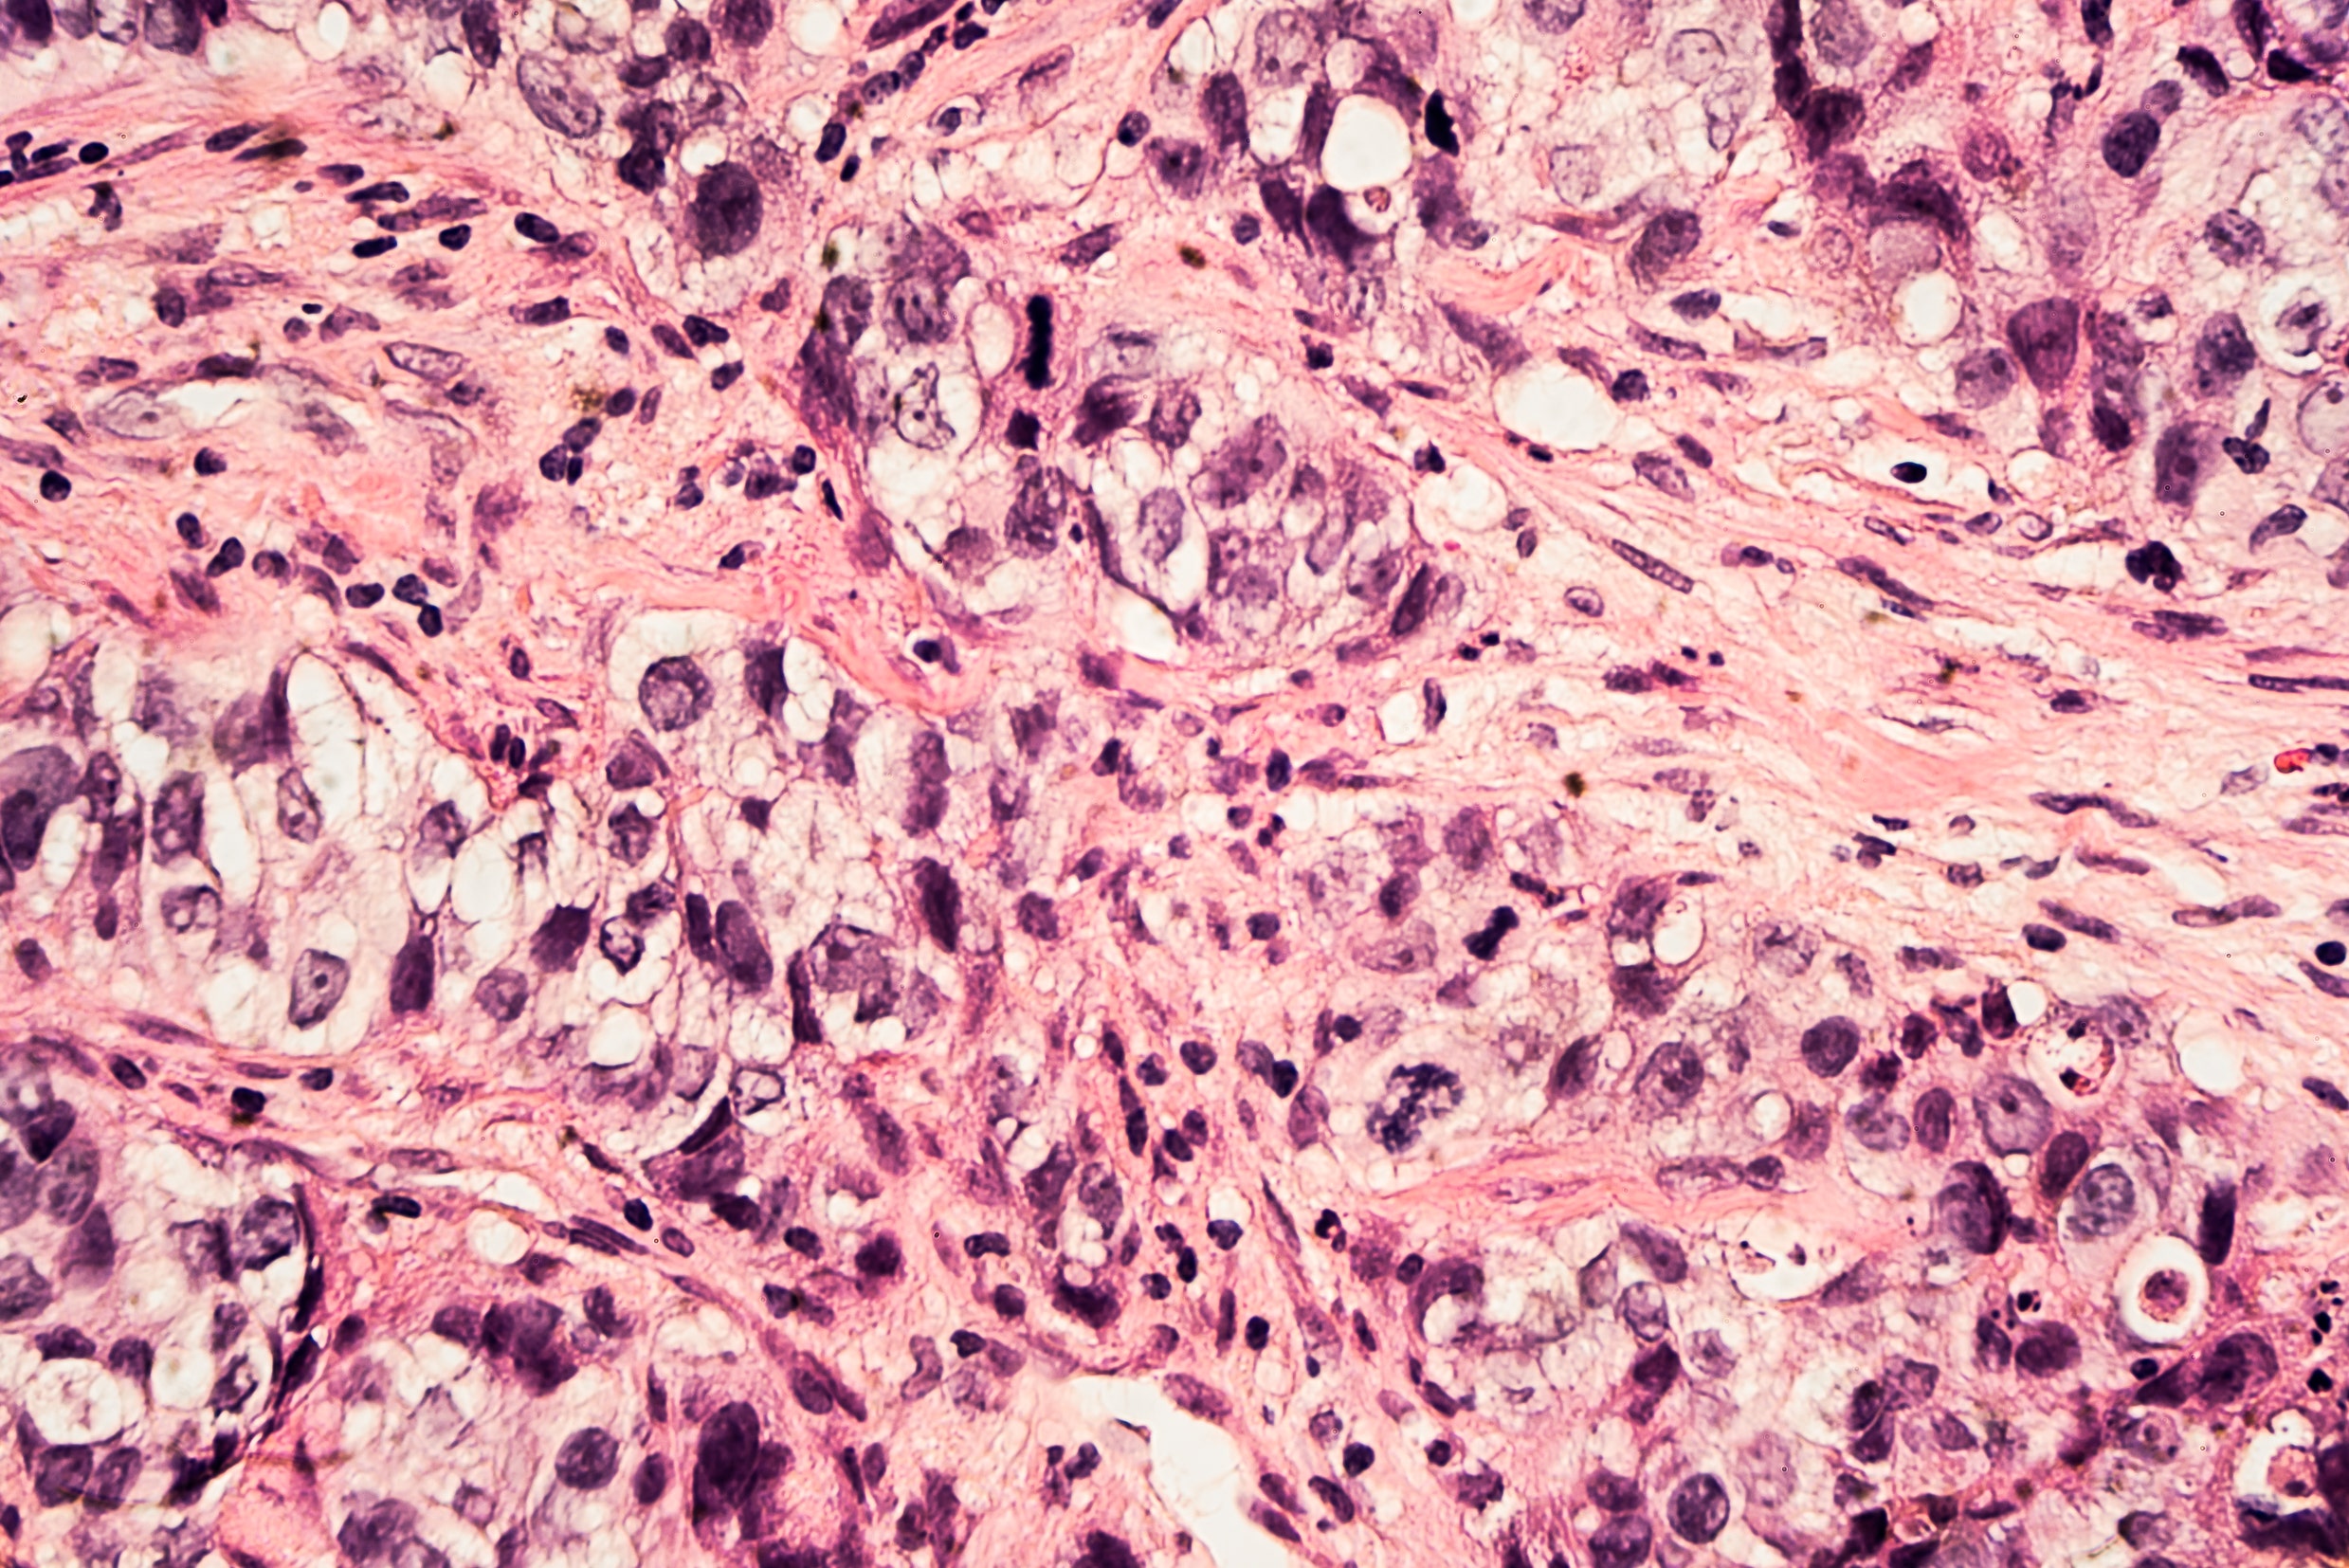

Раздел: Снимки-откровения